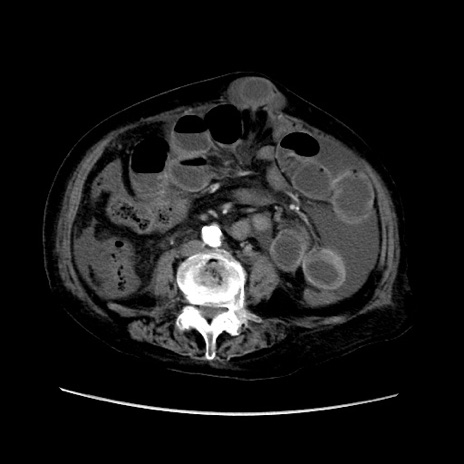

症例31(横断像)

【症例】80歳代 女性

【主訴】腹部膨満感

【現病歴】他院にて肝硬変にてフォロー中。1週間前から便秘、腹部膨満感、臍部腫瘤あり受診となる。

【既往歴】肝硬変

【身体所見】腹部膨隆あり、皮膚変化なし、疼痛なし。

【データ】WBC 4600、CRP 0.25